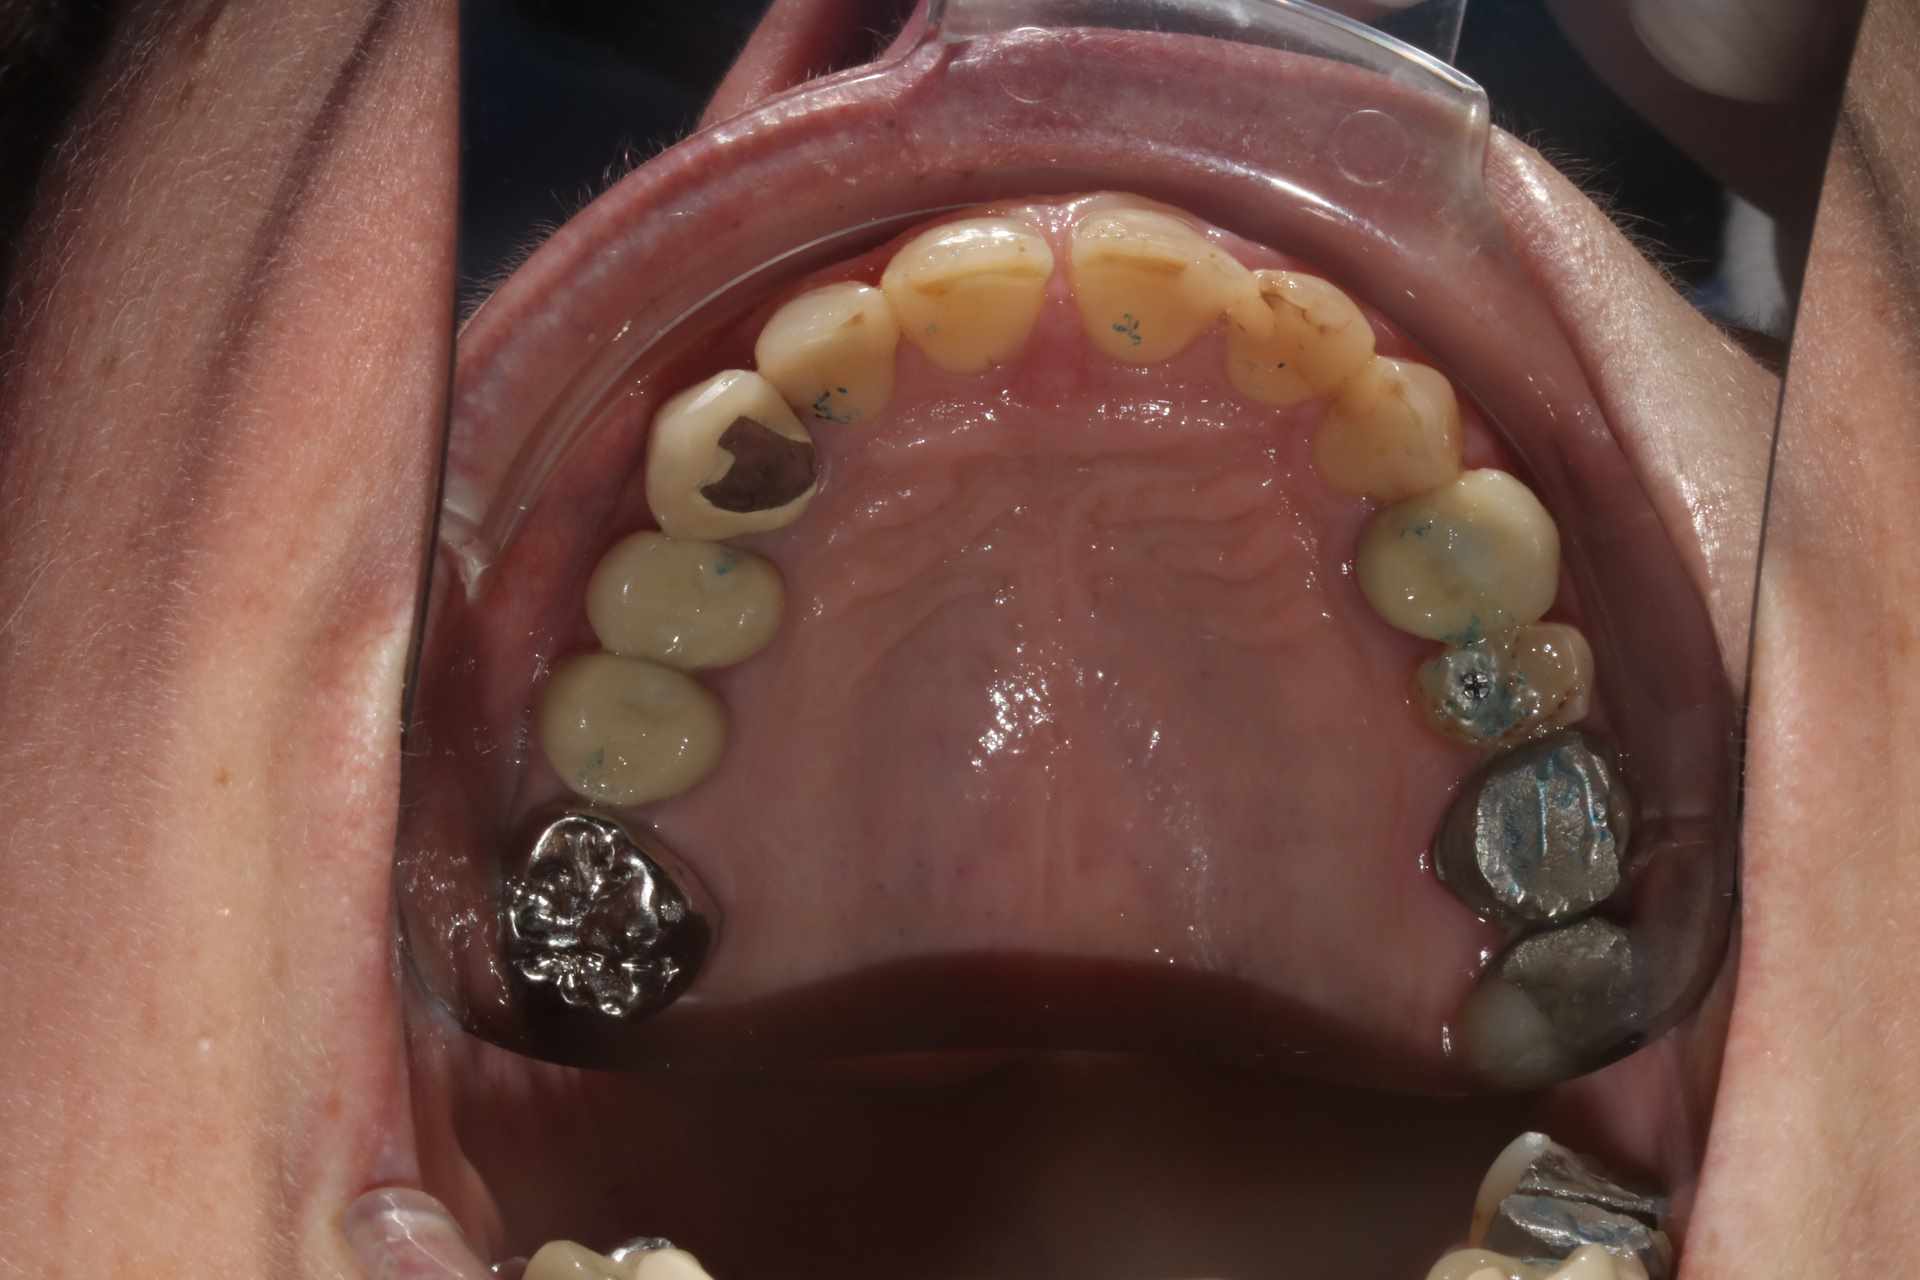

La patiente venait pour 34 35 descellées et 13 mobile. J'en suis encore au stade on traite les urgences avant de s'attaquer vraiment au cas. Vous voulez pas me donner un coup de main ? je ne sais pas trop par ou commencer !

On a une classe 2 2 majeure. ultra verrouillée. Je ne vois pas comment m'en sortir sans augmenter la DV qui a été malmenée par les soins et couronnes diverses a peu près tous en sous occ à mon avis sauf la 13 qui a explosé.

2) Comme Algi, on voit la tête du maxillaire. Réévaluation de 13 (probablement fracturée non conservable). Evaluation de la (des) courbe d'occlusion. Les antérieures sont un peu courtes mais c'est de l'usure, si ça ne gène pas la patiente, pas touche.

A mon avis on va être bon pour (re)faire les couronnes sur 4-5-6 de chaque coté (+ la 7 qui reste) qui semblent bien basses. Je pense qu'on a une perte de 1 à 2 mm à vu de nez en comparant avec les antérieures. Sauf la 24 qui a l'air à peu près OK en terme de DV mais on peut refaire quand même.

Je ne suis pas certain qu’il y ait eu tant de perte de DV. Ce serait à vérifier avec d’anciennes photos ou panos.

Je dis ça parce qu’ on constate quand même peu d’usure sur les dents encore saines et elle a une fameuse supra-alvéolie maxillaire.

Oui la couronne sur sur 13 c'est une honte, volumineuse et beaucoup trop longue. Je suspecte une couronne faite avec un mordu unilatéral pour expliquer une telle aberration.

Sur 34 35 il y avait des couronnes jumelées qui se sont descellées peu après que la 13 se descellée / fracture.